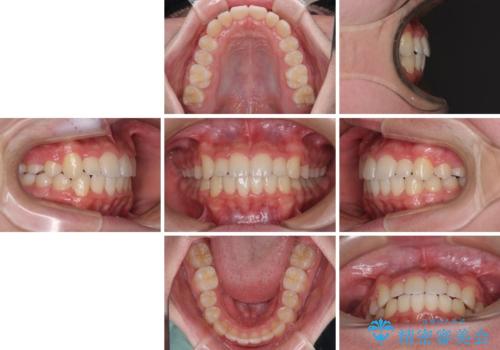

中学生のワイヤー矯正 クロスバイトを短期間で改善

叢生のため磨き残しの多い歯列でしたが、1年弱で治療を終了でき、磨き残しや歯肉の腫れが著しく改善されました。